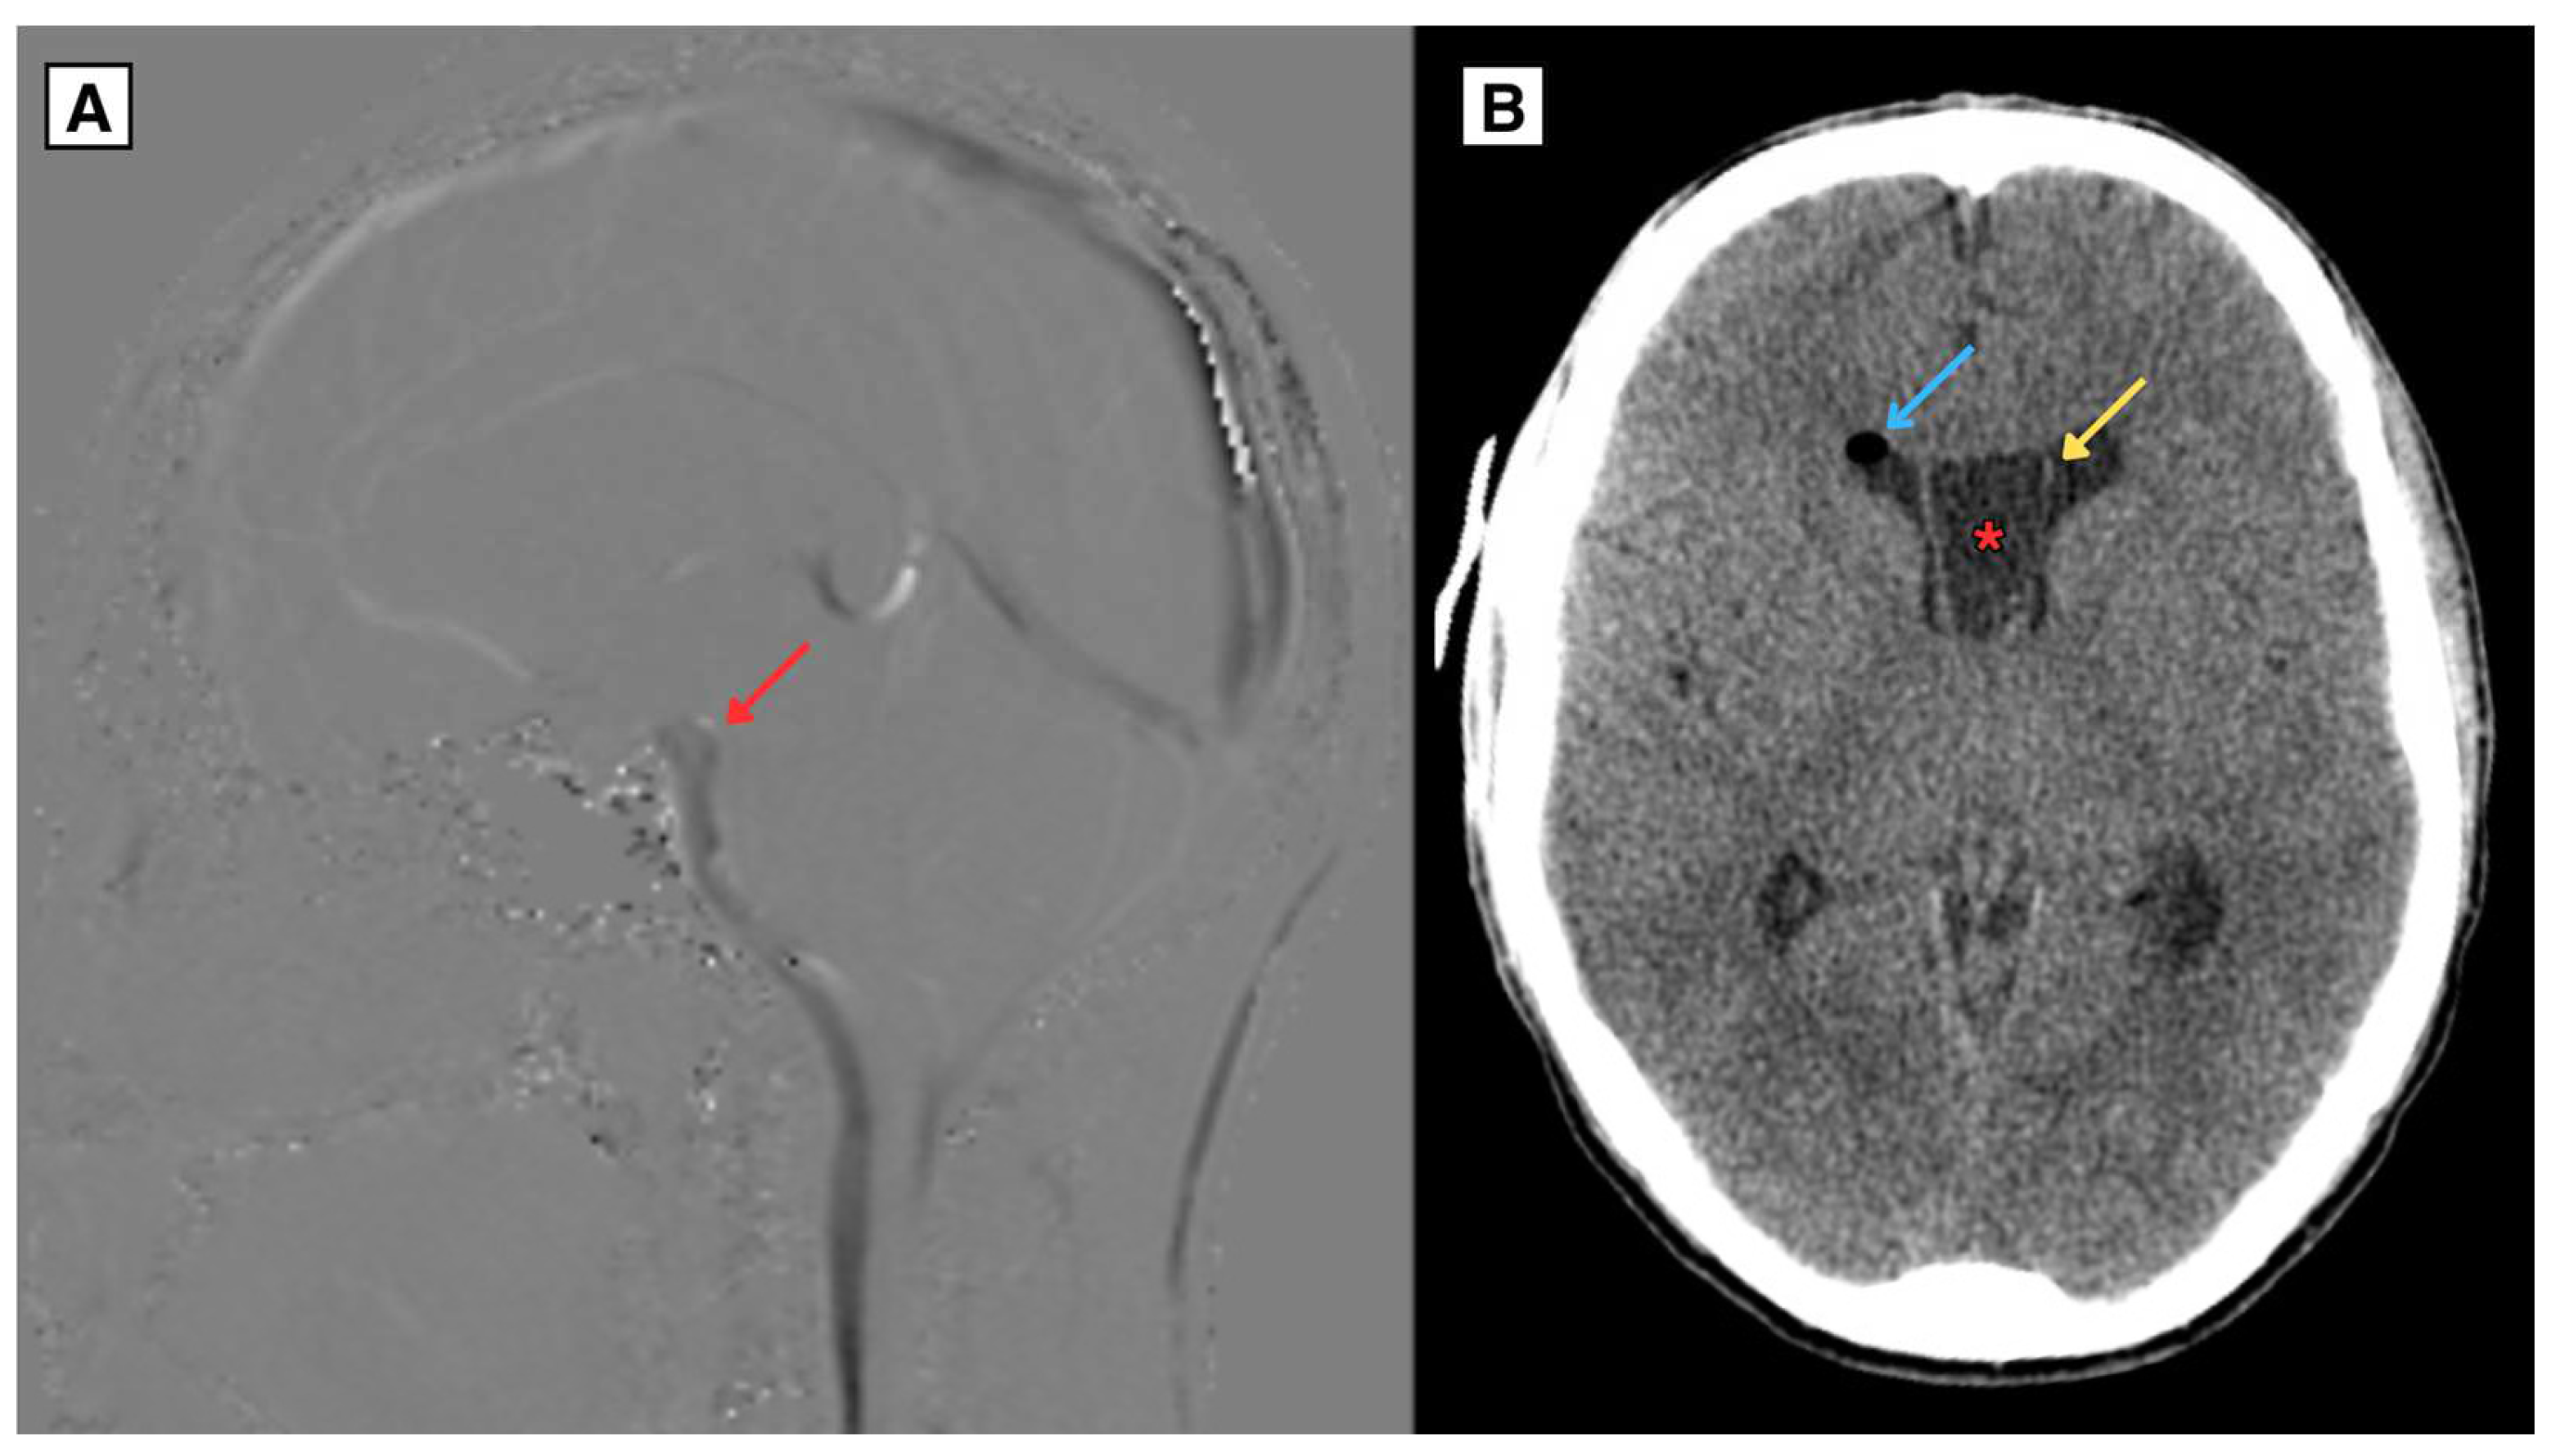

2.1. Retrospective imaging Review

2.2. A Novel Anatomical Pattern in CSP Cyst Imaging